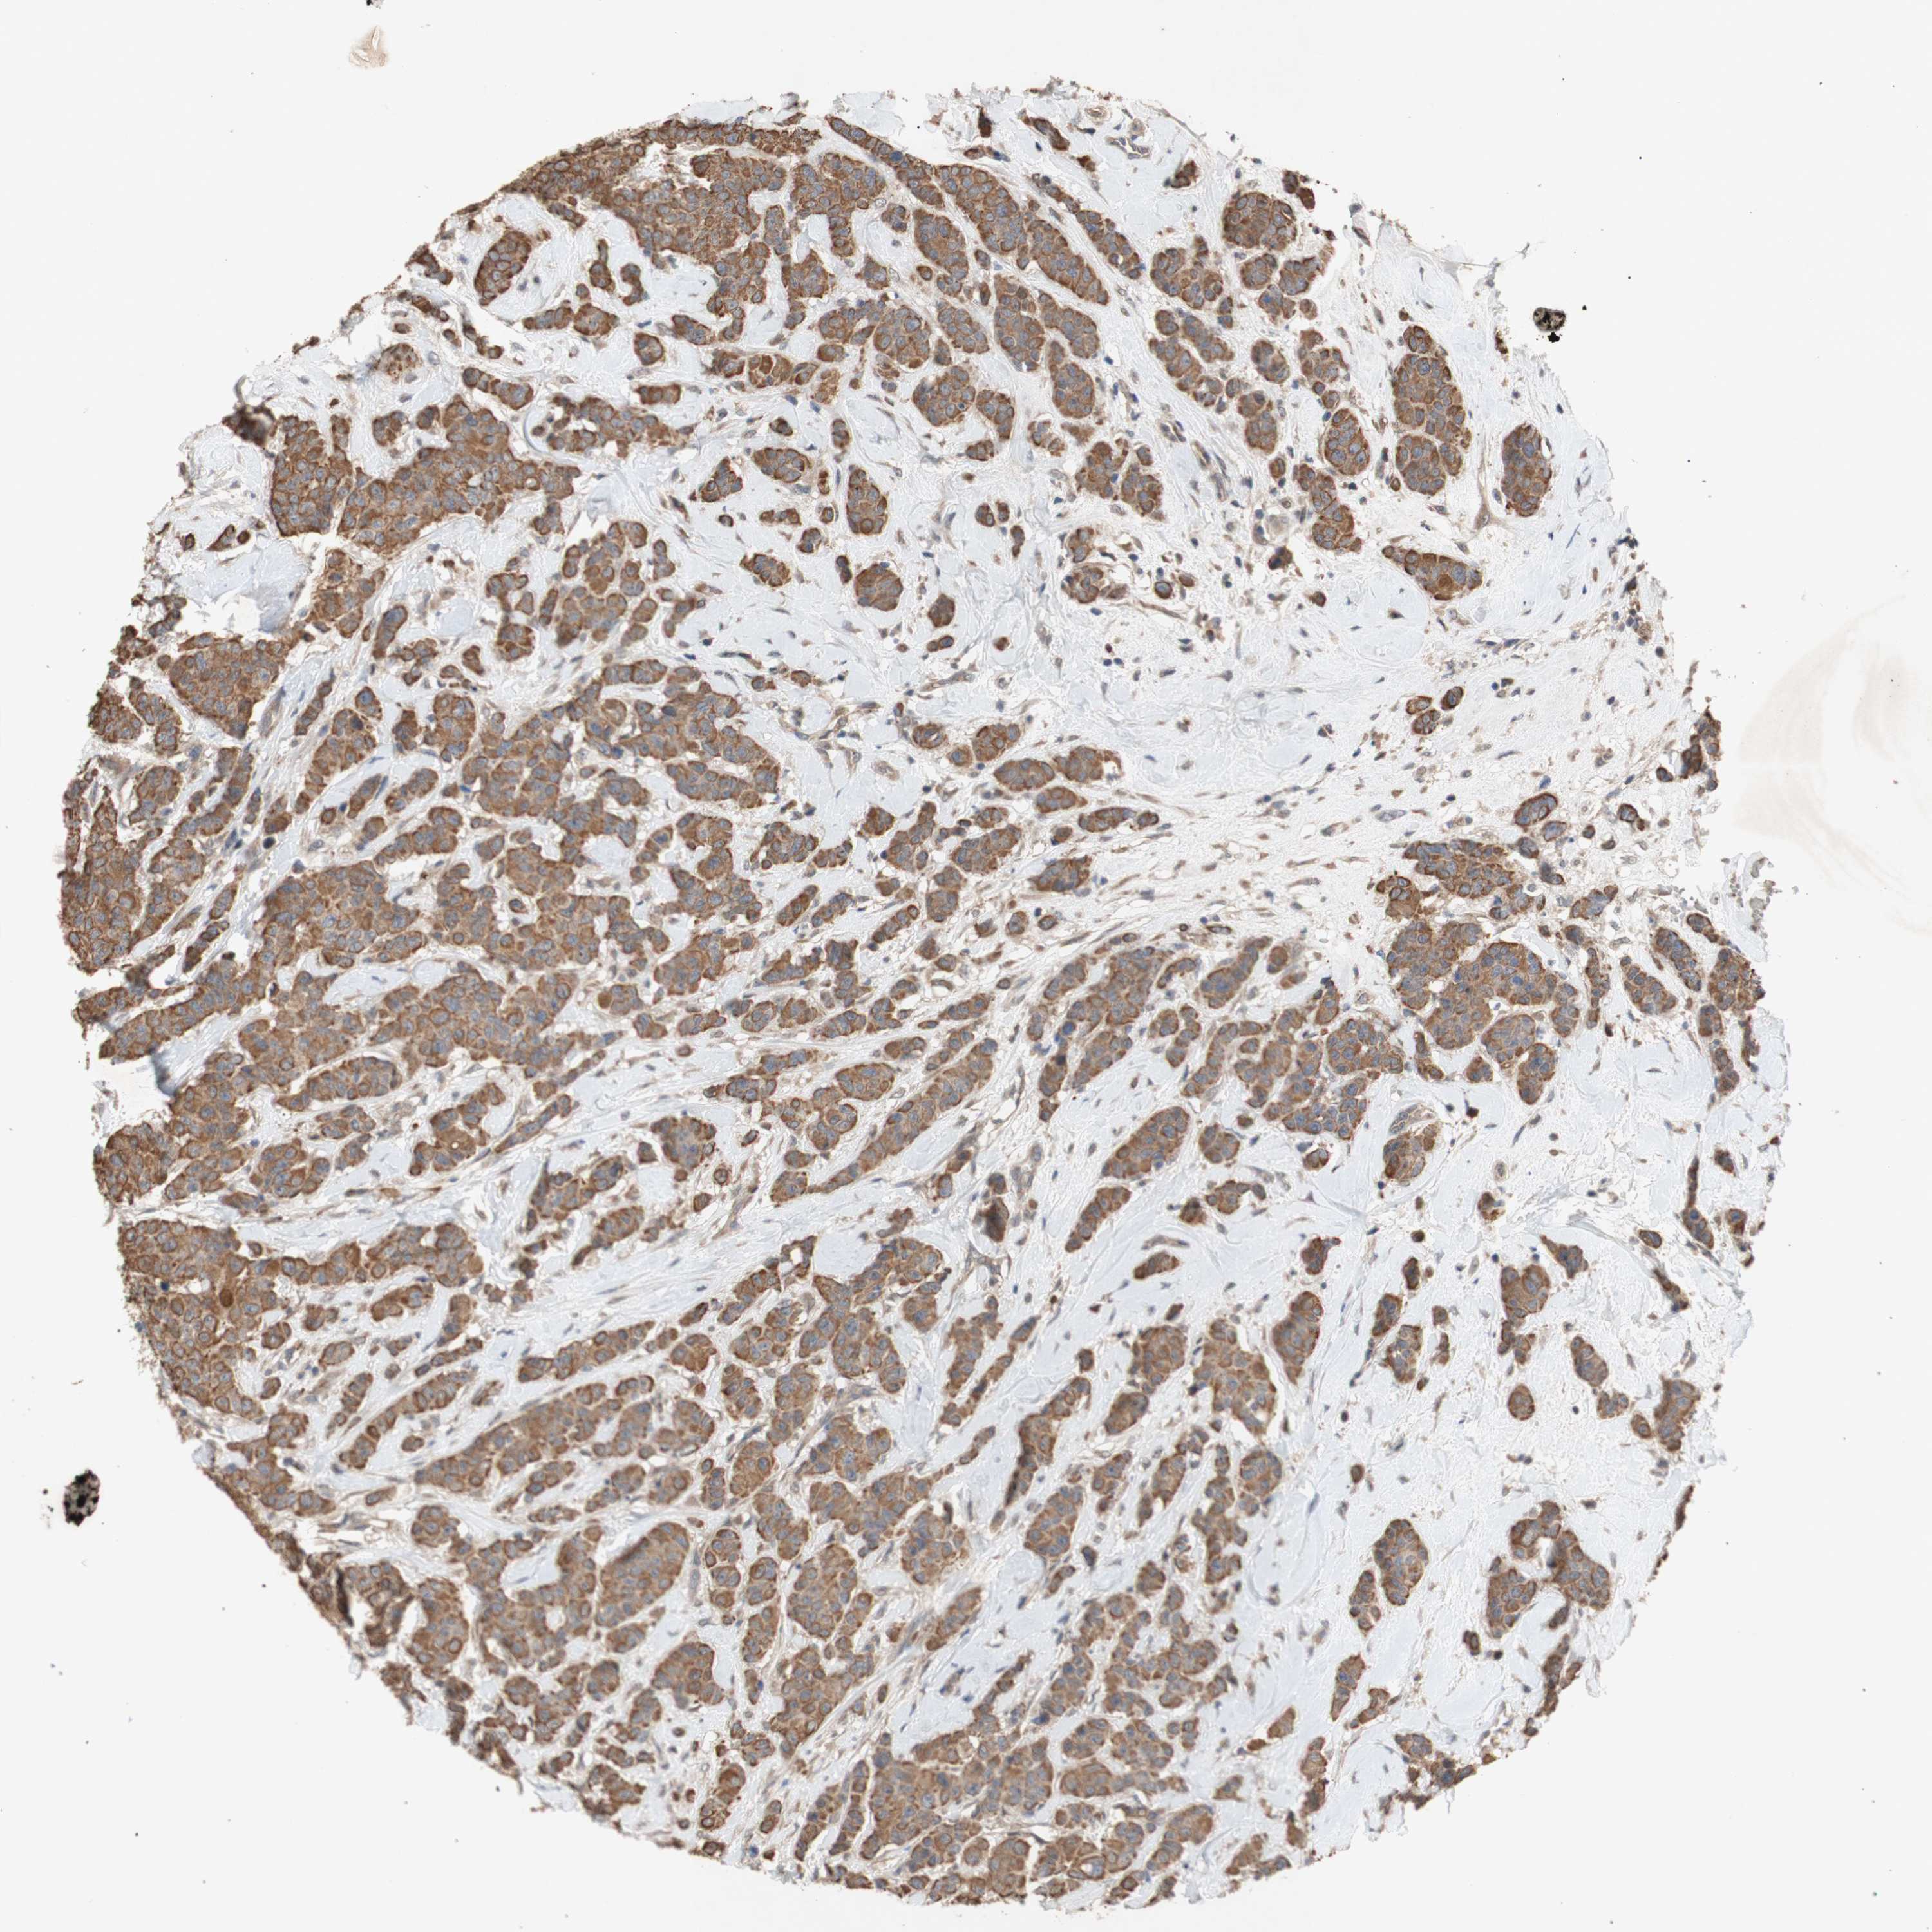

CANCER BREAST CANCER Show tissue menu

BRCA TCGA BRCA VALIDATION PROTEIN EXPRESSION

ANTIBODIES

AND

VALIDATION